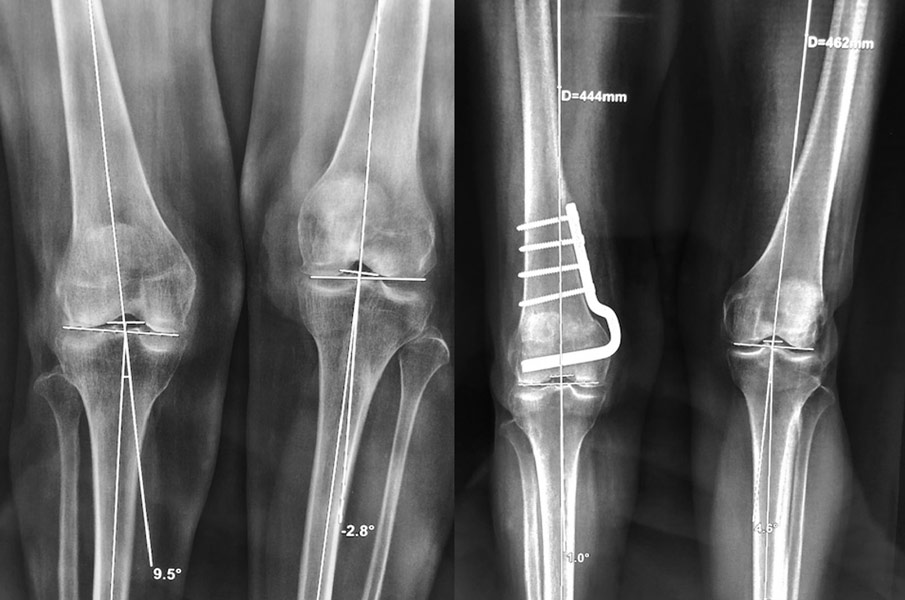

Patiente opérée à l’âge de 30 ans d’une rupture du ligament croisé antérieur. Arthrose progressive. Handicap important.

2ème opération à l’âge de 40 ans, du fait d’une arthrose interne du genou, par ostéotomie tibiale de valgisation. Excellent résultat 10 ans après

10 ans après l’ostéotomie, excellent résultat : aucune douleur, mobilités normales.